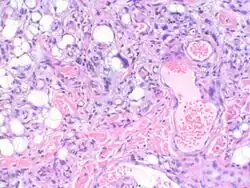

Myxofibrosarcoma-pathology